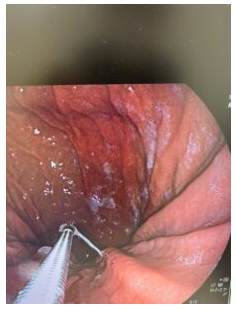

鉗子(組織をつまむ器材)でアニサキスをつまみます。

無事に胃壁からアニサキス虫体の除去に成功しました。

そのまま落とさないように体外に出します。

当クリニックでは、鎮静剤を使用して眠った状態で胃カメラ検査をするため、患者様は苦痛を感じません。

検査終了後、鎮静から覚めた患者様は「もう終わったんですか??ずっと寝ていました!!」と驚きの声を上げました。

アニサキスがいてしっかり取り除いた旨を伝えると、「うわー、生きてますね、先生、有難うございます!!」と安堵の表情を浮かべます。

緊急の胃カメラでしたが、胃痛の原因であるアニサキスを除去したため、だんだん痛みが和らぎ症状が劇的に改善していくのは間違いありません。